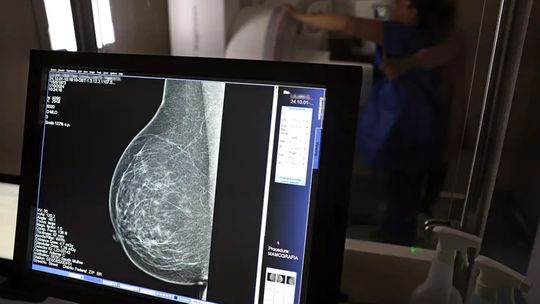

Câncer de mama: uma em cada três pacientes tem menos de 50 anos

Faixa etária concentrou 22% das mortes pela doença entre 2018 e 2023